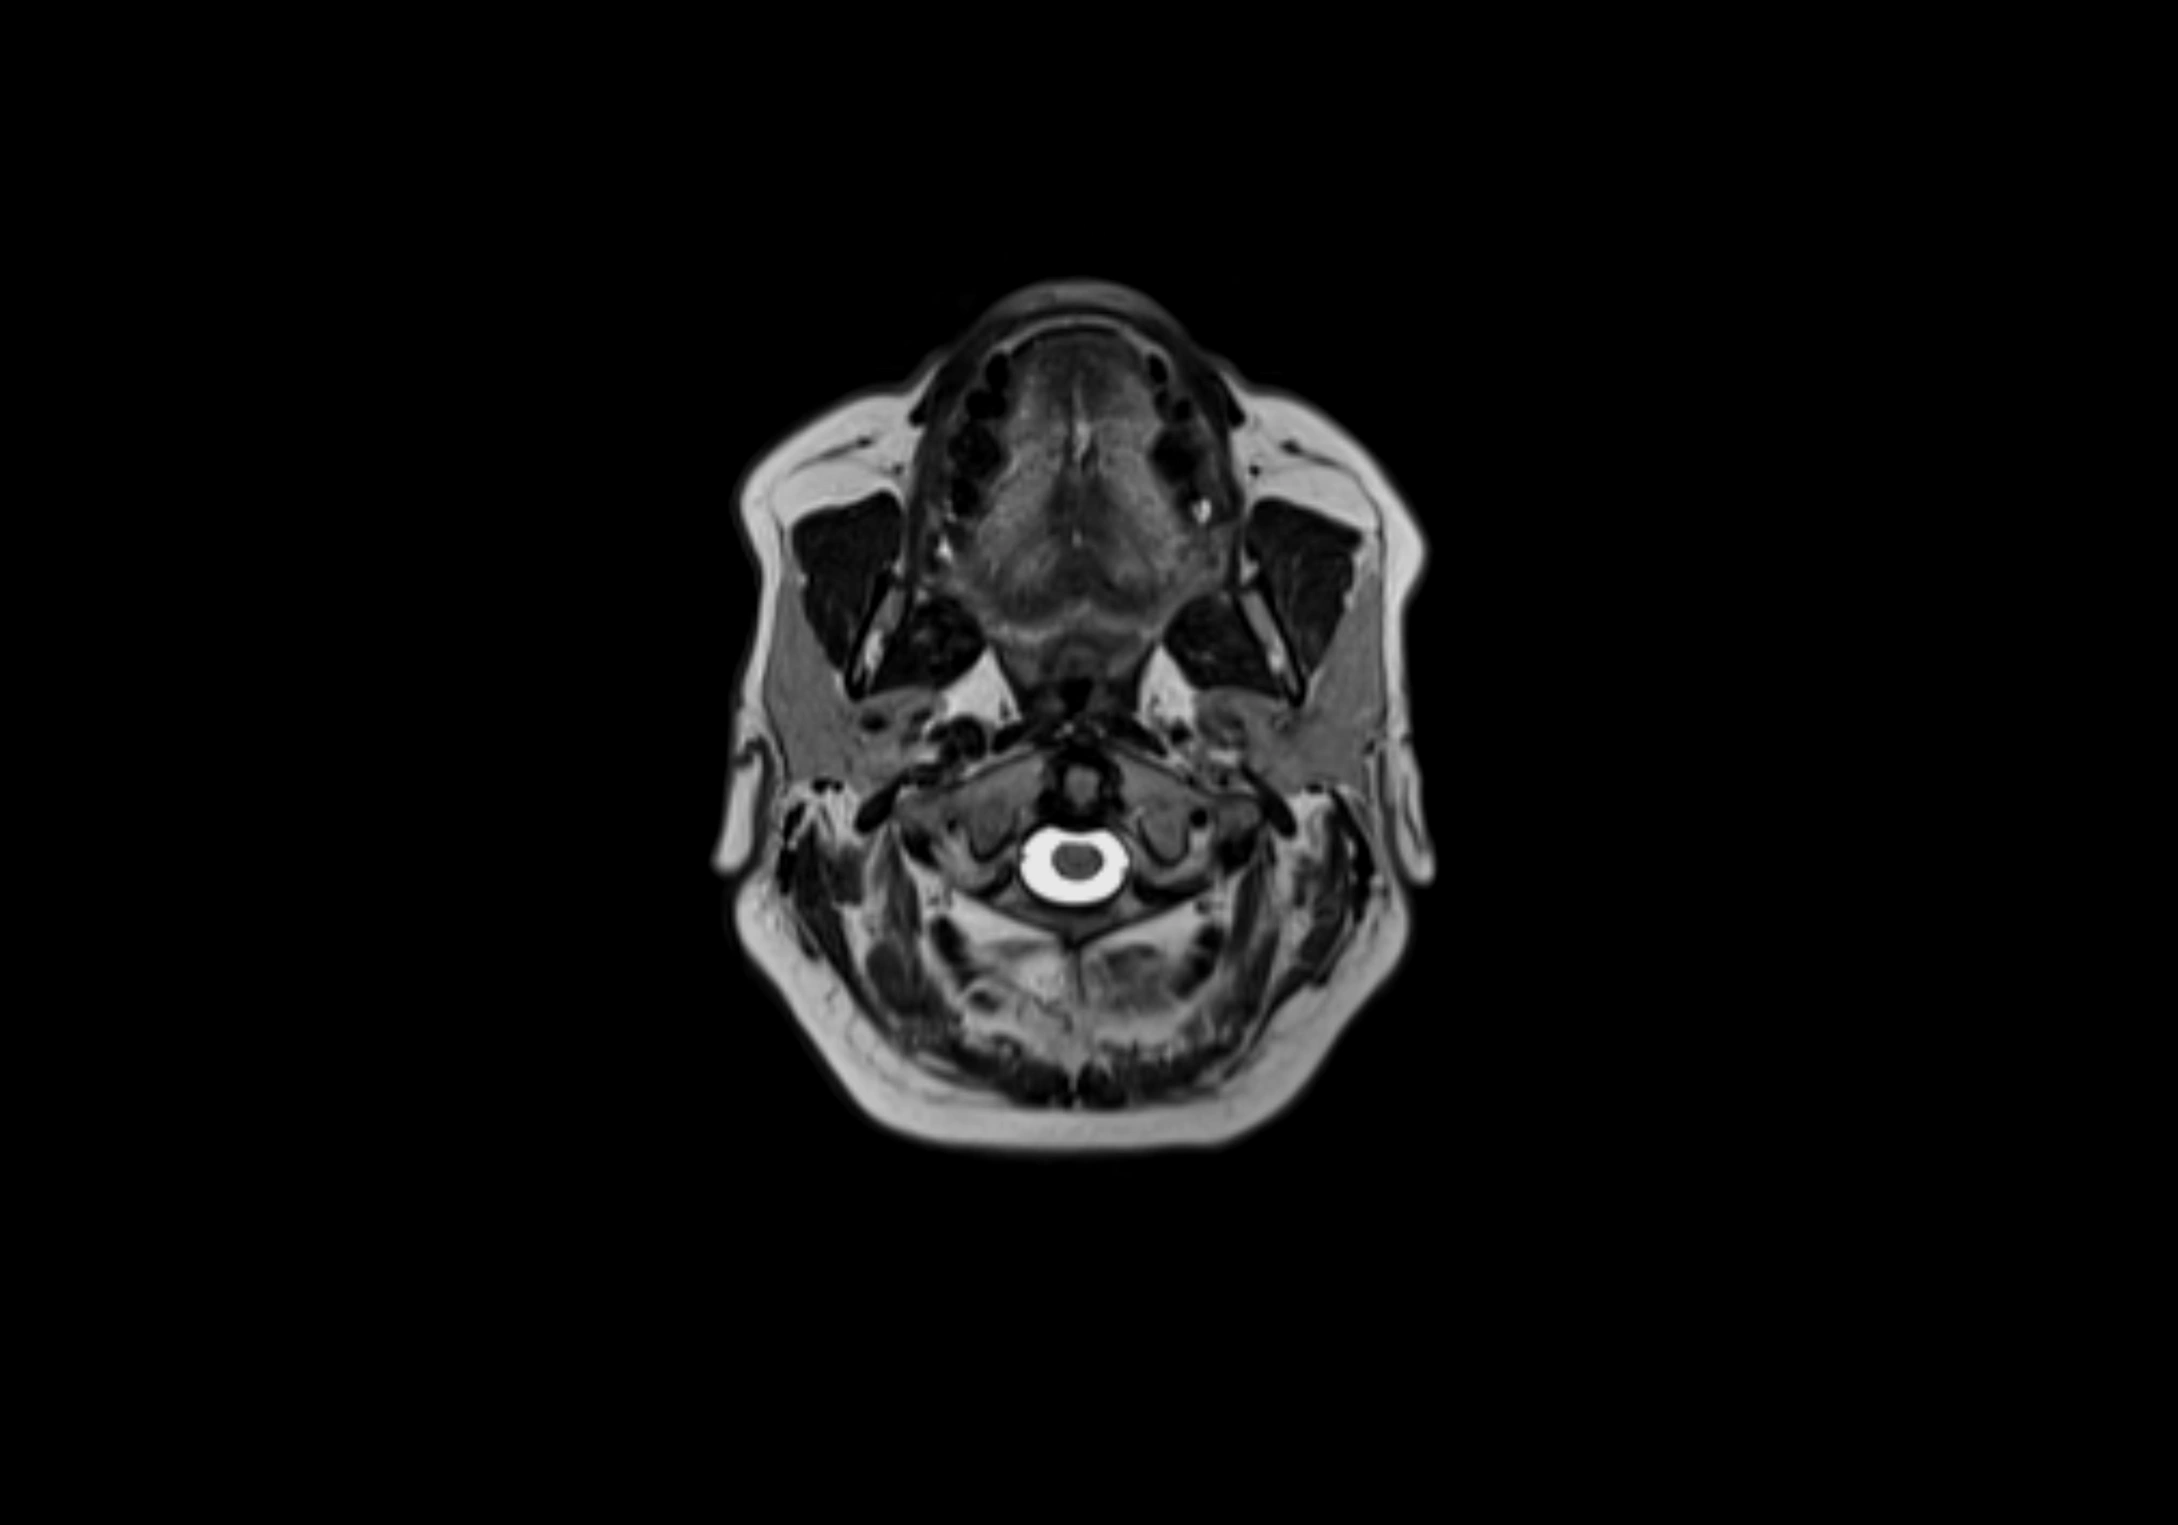

MRI Appearance

T1-weighted images:

• Normal accessory nodes appear as small, oval hypointense to intermediate signal structures within subcutaneous fat

• Surrounded by hyperintense fat, enhancing contrast for visualization

• Pathological nodes may appear enlarged or rounded, sometimes with cortical thickening

MRI images